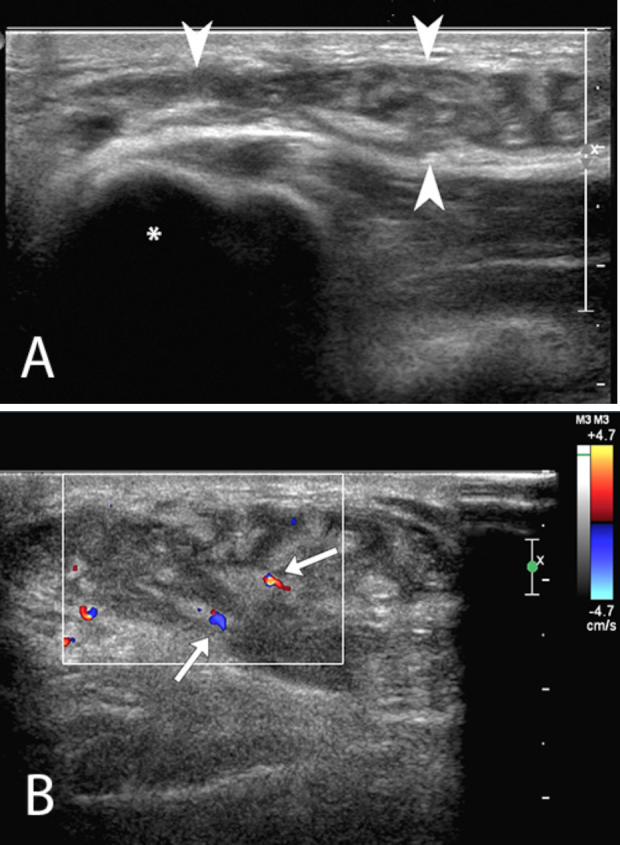

Figure 2.

A. Targeted ultrasound evaluation of the soft palpable mass located over medial epicondyle (asterisk) with a high-frequency linear transducer (12 to 5-MHz transducer) demonstrates a complex collection (arrowheads) located between the subcutaneous fat and fascia. The lesion contains highly echogenic lobules of fat, interspersed with areas of lower echogenicity. B. Color Doppler imaging of the Morel-Lavallée lesion demonstrates minimal flow in two small vessels (arrows) traversing the collection, and absence of flow in the lesion otherwise.

On ultrasound, the mass showed lobules of increased echogenicity, interspersed with areas of slightly complex lower echogenicity. Unenhanced MRI, performed the following week, demonstrated an irregularly shaped, 4.2 × 3.7 × 1.4-cm (longitudinal × AP × transverse) lentiform unilocular T2 hyperintense collection that contained numerous fat globules overlying the deep fascia of the elbow and draping over the medial epicondyle (Figure 3, Figure 4).